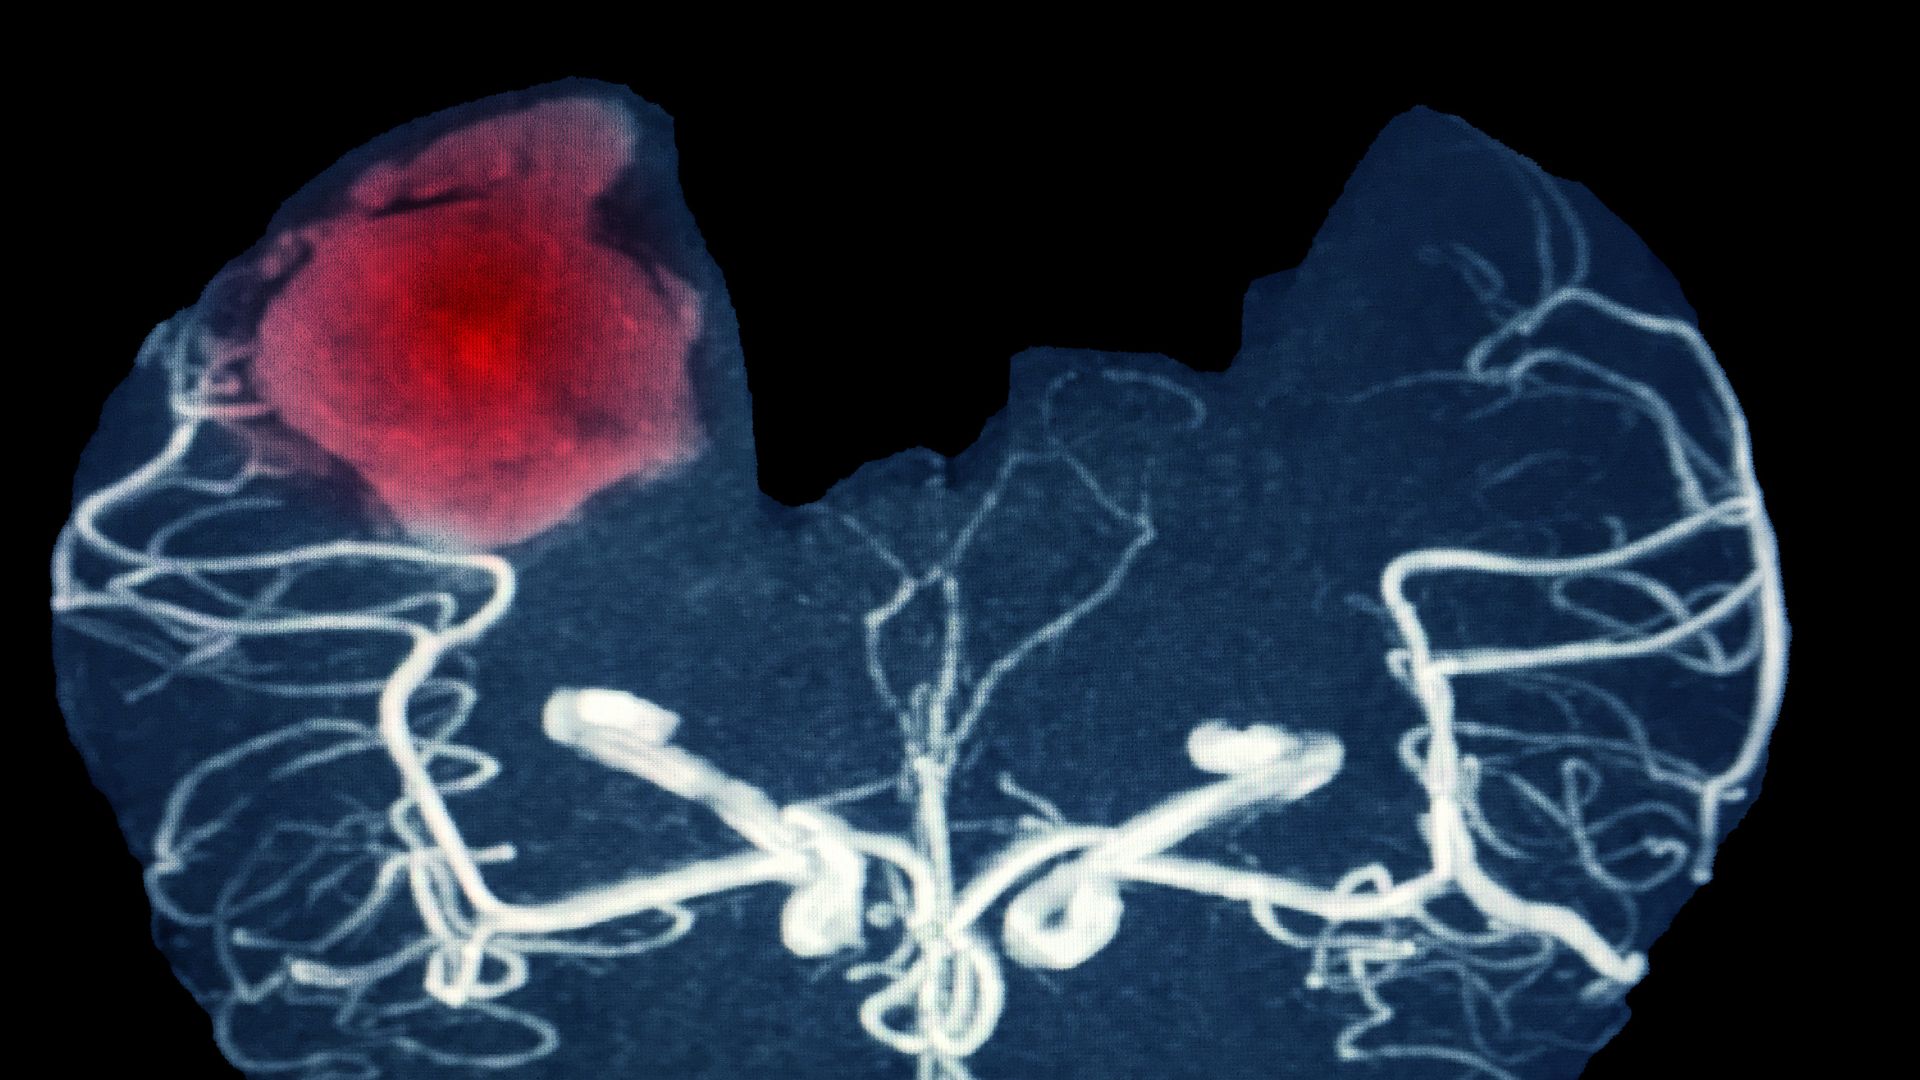

Dự phòng xuất huyết não mùa lạnh

Xuất huyết não là một cấp cứu thần kinh cực kỳ nguy hiểm, có thể gây tử vong nhanh hoặc để lại di chứng nặng nề. Vào mùa lạnh, nguy cơ này tăng cao hơn do nhiệt độ thấp khiến mạch máu co lại, huyết áp tăng đột ngột và cơ thể phản ứng mạnh trước sự thay đổi nhiệt độ. Vì vậy, chủ động phòng ngừa trong giai đoạn này là vô cùng cần thiết, đặc biệt ở người cao tuổi và những người có bệnh nền.